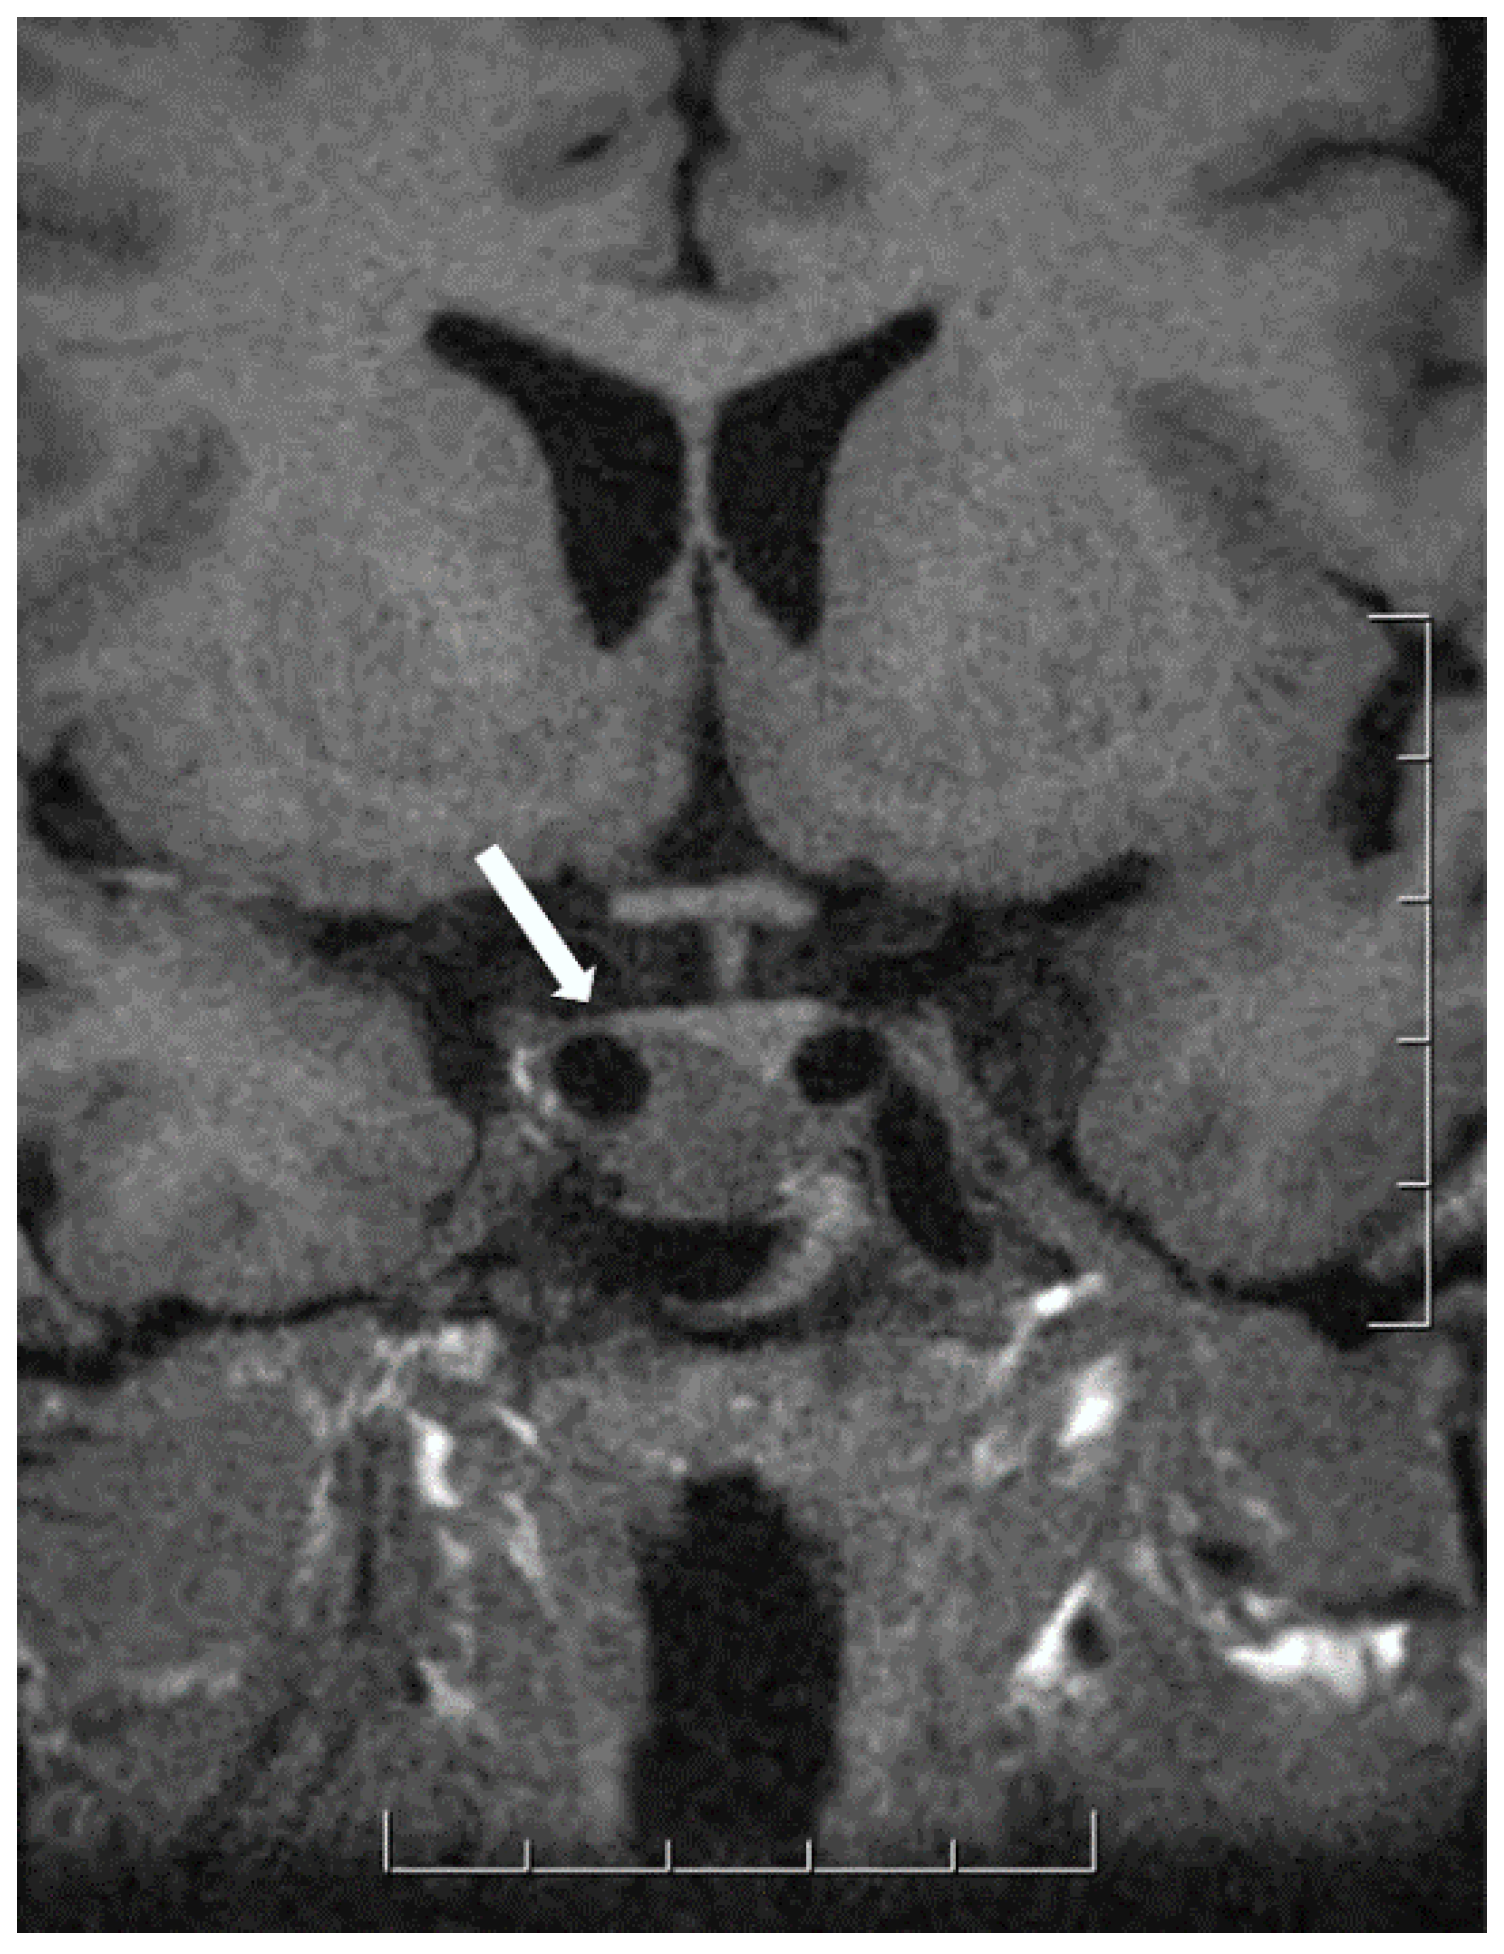

- Heck, A.; Ringstad, G.; Fougner, S.L.; Casar-Borota, O.; Nome, T.; Ramm-Pettersen, J.; Bollerslev, J. Intensity of pituitary adenoma on T2-weighted magnetic resonance imaging predicts the response to octreotide treatment in newly diagnosed acromegaly. Clin. Endocrinol. (Oxf.) 2012, 77, 72–78. [Google Scholar] [CrossRef]

- Hagiwara, A.; Inoue, Y.; Wakasa, K.; Haba, T.; Tashiro, T.; Miyamoto, T. Comparison of growth hormone-producing and non-growth hormone-producing pituitary adenomas: Imaging characteristics and pathologic correlation. Radiology 2003, 228, 533–538. [Google Scholar] [CrossRef] [PubMed]

- Potorac, I.; Petrossians, P.; Daly, A.F.; Alexopoulou, O.; Borot, S.; Sahnoun-Fathallah, M.; Castinetti, F.; Devuyst, F.; Jaffrain-Rea, M.L.; Briet, C.; et al. T2-weighted MRI signal predicts hormone and tumor responses to somatostatin analogs in acromegaly. Endocr. Relat. Cancer 2016, 23, 871–881. [Google Scholar] [CrossRef] [PubMed]

- Mete, O.; Gomez-Hernandez, K.; Kucharczyk, W.; Ridout, R.; Zadeh, G.; Gentili, F.; Ezzat, S.; Asa, S.L. Silent subtype 3 pituitary adenomas are not always silent and represent poorly differentiated monomorphous plurihormonal Pit-1 lineage adenomas. Mod. Pathol. 2016, 29, 131–142. [Google Scholar] [CrossRef]

- Horvath, E.; Kovacs, K.; Smyth, H.S.; Cusimano, M.; Singer, W. Silent adenoma subtype 3 of the pituitary--immunohistochemical and ultrastructural classification: A review of 29 cases. Ultrastruct. Pathol. 2005, 29, 511–524. [Google Scholar] [CrossRef]

- Erickson, D.; Scheithauer, B.; Atkinson, J.; Horvath, E.; Kovacs, K.; Lloyd, R.V.; Young, W.F., Jr. Silent subtype 3 pituitary adenoma: A clinicopathologic analysis of the Mayo Clinic experience. Clin. Endocrinol. (Oxf.) 2009, 71, 92–99. [Google Scholar] [CrossRef]